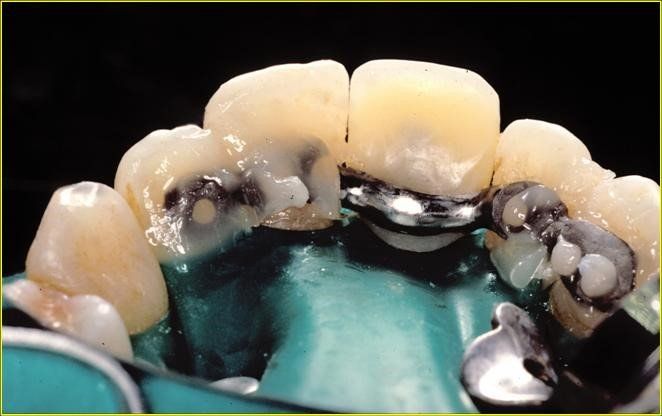

Arcata superiore destinata all’estrazione di tutti gli elemti dentali residui.

Spesso si è discusso sulla natura dei denti che devono essere applicati alla struttura. La modalità classica di trattamento prevede la costruzione di Toronto Bridge con denti in resina. L’utilizzo della ceramica deve essere evitato nella costruzione di arcate complete come nel caso appunto dell’edentulia completa. La necessità di accomodamenti relative ai contatti con l’arcata antagonista richiede un materiale che si lasci plasmare come la resina mentre la ceramica essendo troppo dura non lo consentirebbe dando origine ad una distribuzione delle forze masticatorie non controllata. Un aspetto importante è costituito dal fatto che venga mantenuto uno spazio tra Toronto Bridge e gengiva sottostante sufficiente al passaggio dei dispositivi di igiene orali dei quali il protagonista è senza dubbio lo scovolino interdentale che verrà scelto nella misura adeguata settore per settore.

Visione clinica del Maryland bridge cementato con tecnica adesiva ed immagine tomografica tridimensionale per valutare lo spessore bucco palatale utile all’inserimento dell’impianto che fu valutato come sufficiente benchè esiguo. A tal proposito deve essere sottolineato che la letteratura consiglia, quando è disponibile un volume di osso residuo utile all’inserimento di un impianto, di evitare tecniche di innesto osseo in quanto un aumento dei volumi ossei non migliora la prognosi estetica (3)